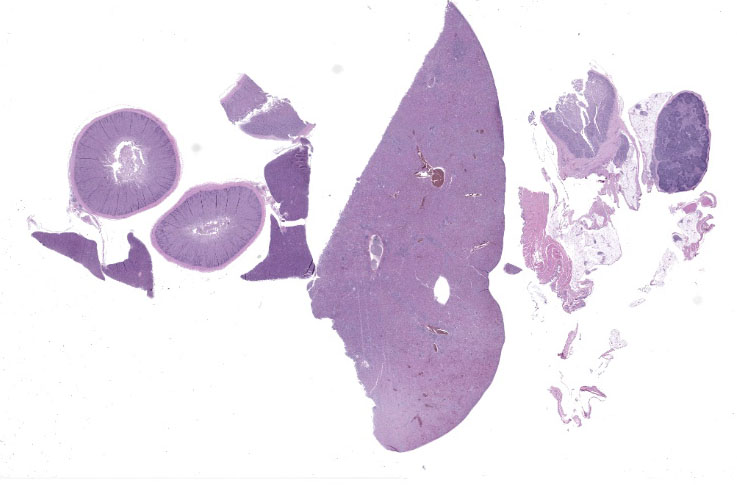

Liver: Surrounding portal regions and occasionally coalescing are infiltrates of moderate numbers of lymphocytes and histiocytes that disrupt the hepatic architecture. Within the lymphocytes and histiocytes are numerous, 2 um in diameter, basophilic protozoal organisms surrounded by a thin, clear halo that peripheralizes the nucleus. The inflammatory cells separate and individualize the hepatocytes, which display mild karyomegaly and frequent binucleation. Free within the sinusoidal lumina and within portal and central veins are numerous, approximately 5 um diameter, pyriform flagellate protozoa with a single, variably distinct nucleus. Occasional large lymphocytes and rare plasma cells circulate throughout the sinusoids.

Liver: Moderate, multifocal, chronic, lymphohistiocytic hepatitis with intracellular protozoa (consistent with isosporosis, Isospora sp) and sinusoidal flagellates

1. Liver: Cholangiohepatitis, histiocytic and lymphoplasmacytic, chronic, diffuse, marked, with intrahistiocytic apicomplexan zoites and sinusoidal flagellates.

2. Duodenum: Enteritis, histiocytic, chronic, diffuse, severe, with intrahistiocytic apicomplexan zoites.

3. Cloaca: Cloacitis, proliferative and histiocytic, chronic, diffuse, marked, with numerous luminal flagellates.

4. Bursa of Fabricius: Bursitis, necrotizing, chronic, multifocal, mild, with intraluminal flagellates.